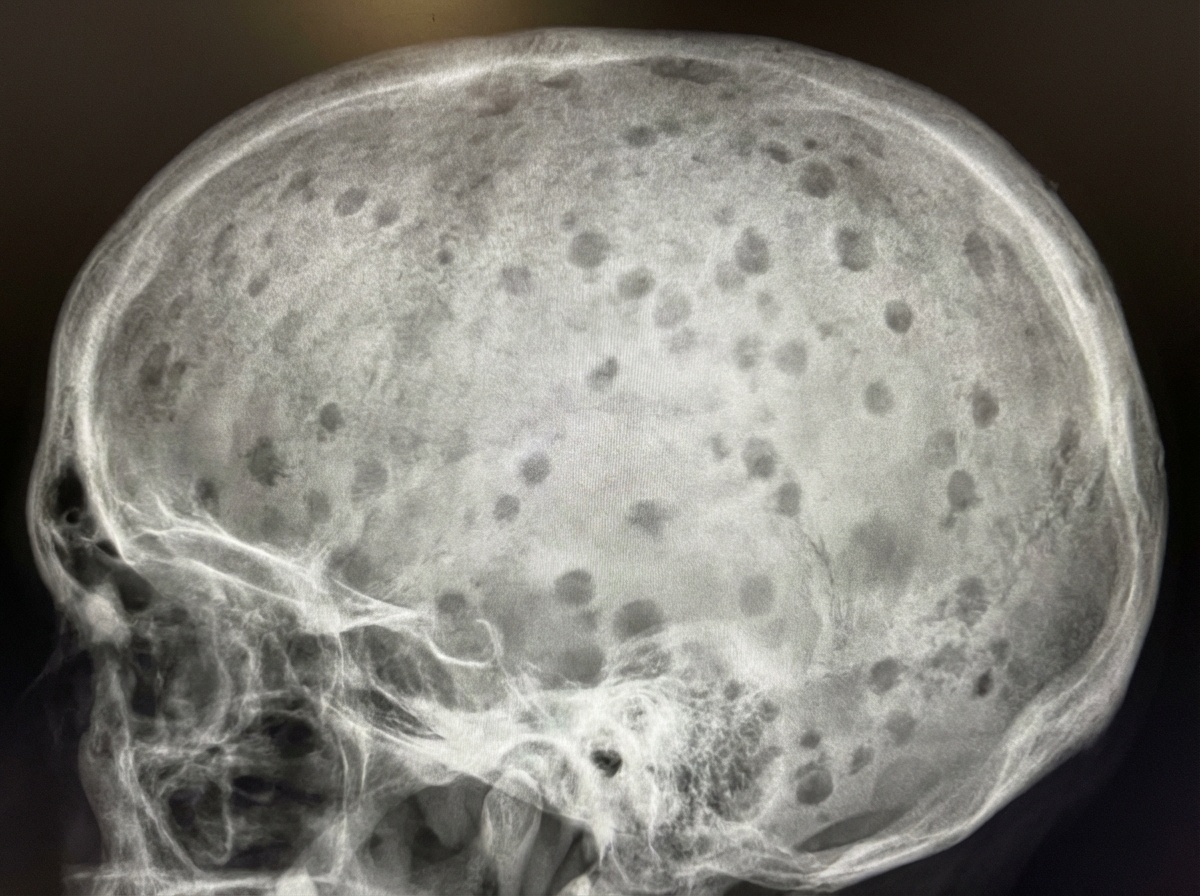

What is shown in the X-ray skull?

Explanation: ***Pepper pot skull*** - Characterized by **multiple small punched-out lytic lesions** throughout the skull, giving a characteristic "salt and pepper" appearance on X-ray. - Commonly associated with **hyperparathyroidism** and **multiple myeloma**, where bone destruction creates numerous small radiolucent areas. *Artifacts* - Result from **technical errors** during X-ray acquisition, such as patient movement, equipment malfunction, or processing issues. - Present as **irregular patterns** or distortions that don't follow anatomical structures and can be reproduced with repeat imaging. *Silver-beaten appearance* - Shows **generalized thinning** of the inner table of the skull with a beaten metal-like appearance on X-ray. - Associated with **raised intracranial pressure** in children, causing chronic pressure effects on the developing skull. *Mug shot with pellets* - Refers to **retained metallic foreign bodies** (like shotgun pellets) visible as **radiopaque densities** on skull X-ray. - Appears as **discrete, well-defined metallic objects** with characteristic shape and density, not the diffuse lytic pattern seen here.

Explanation: ### Explanation The **'hair-on-end'** (or crew-cut) appearance is a classic radiological sign seen on a lateral skull X-ray. It occurs due to **compensatory extramedullary hematopoiesis** in response to chronic hemolytic anemia. **1. Why Thalassemia is Correct:** In conditions like **Thalassemia Major** and **Sickle Cell Anemia**, the body attempts to compensate for chronic hypoxia and ineffective erythropoiesis by expanding the bone marrow. This causes: * **Widening of the diploic space** of the skull. * **Thinning of the outer table.** * The formation of new bone trabeculae perpendicular to the inner table, which creates the characteristic "sunburst" or "hair-on-end" vertical striations. **2. Why Other Options are Incorrect:** * **Hydrocephalus:** This typically presents with "beaten silver" or **"copper beaten"** skull appearance due to increased intracranial pressure causing gyral impressions on the inner table of the skull. * **Chronic Malaria:** While malaria causes hemolysis, it rarely leads to the degree of marrow hyperplasia required to produce the hair-on-end sign. * **All of the above:** Incorrect, as the sign is specific to marrow-expanding disorders. **3. High-Yield Clinical Pearls for NEET-PG:** * **Other conditions with 'hair-on-end':** Sickle cell anemia, Hereditary spherocytosis, and occasionally Iron deficiency anemia (rarely in children). * **Facial changes:** Marrow expansion in Thalassemia also involves the maxilla, leading to **"Chipmunk facies"** (prominent cheekbones and malocclusion). * **Note:** The **frontal bone** is most commonly involved, but the **occipital bone** is usually spared because it lacks significant hematopoietic marrow in adults.

Explanation: ### Explanation **Correct Answer: A. Congenital hemolytic anemia** The "hair-on-end" appearance (also known as the crew-cut sign) is a classic radiological finding caused by **compensatory extramedullary hematopoiesis**. In conditions like **Thalassemia major** and **Sickle cell anemia**, chronic hemolysis leads to a massive demand for red blood cell production. This results in: 1. **Marrow Hyperplasia:** The diploic space of the skull expands to accommodate the proliferating bone marrow. 2. **Trabecular Reorientation:** The outer table of the skull becomes thinned, and new bone trabeculae are laid down perpendicular to the inner table to provide structural support, creating the characteristic "brush border" or "hair-on-end" spikes on a lateral X-ray. --- ### Why the other options are incorrect: * **B. Multiple Myeloma:** Typically presents with **"punched-out" lytic lesions** (well-circumscribed, non-sclerotic margins) due to plasma cell infiltration. It does not cause diploic expansion or vertical trabeculations. * **C. Raised Intracranial Tension:** In children, this leads to **sutural diastasis** (widening of sutures) and a **"beaten silver" or "copper beaten" appearance** of the skull vault due to chronic pressure from gyri. * **D. Meningioma:** While it can cause localized hyperostosis (bone thickening) of the overlying skull, it does not produce a generalized hair-on-end appearance across the diploic space. --- ### High-Yield NEET-PG Pearls: * **Thalassemia:** The most common cause of the hair-on-end appearance. It also causes **"Chipmunk facies"** due to maxillary marrow expansion and a "Salt and Pepper" appearance of the skull. * **Sickle Cell Anemia:** Shows similar skull changes but may also feature **H-shaped vertebrae** (Reynold’s sign) due to endplate infarction. * **Note:** The **facial bones** are often spared in Sickle Cell Anemia (due to early marrow conversion to fat) but are heavily involved in Thalassemia, leading to the characteristic malocclusion.